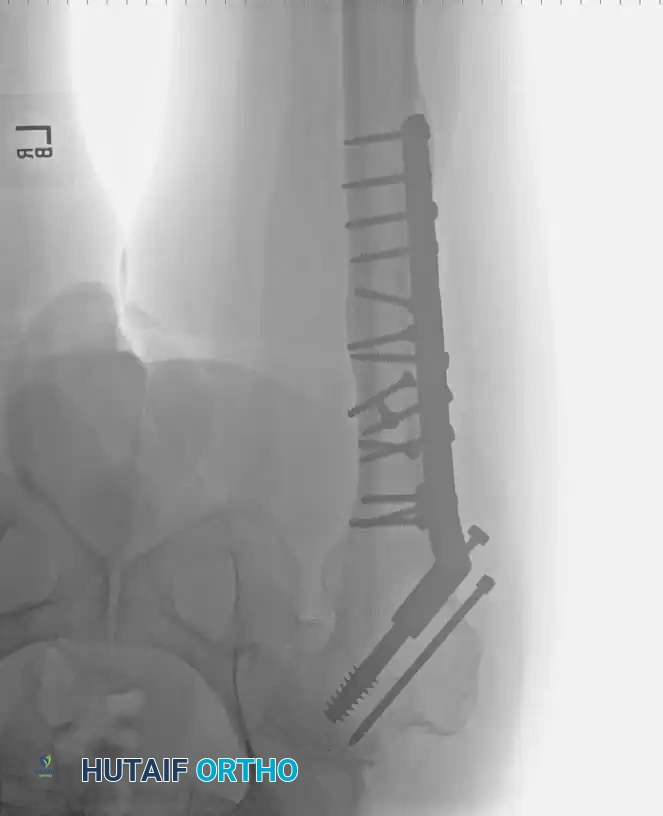

Radiographic Case Examples: Osteoarthritis and Complex Reconstructions

The following imaging series demonstrates various stages of complex acetabular and femoral preparation, highlighting the necessity of restoring offset and center of rotation.

Associated Surgical & Radiographic Imaging

Hutaifortho's Orthopaedic Diagram